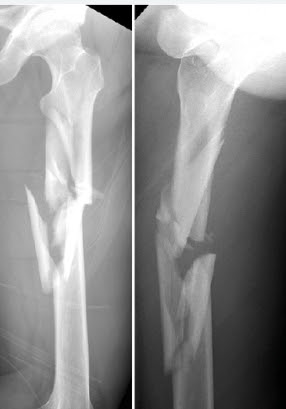

Comminuted fracture - Definition

The fracture breaks into multiple pieces

Comminuted fracture - Cause

Caused through a crushing force

Comminuted fracture